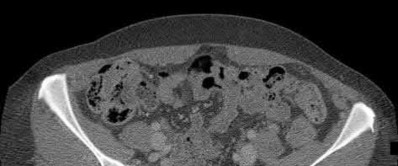

3. # Which of the following is not an appropriate implant for treatment of the fracture seen in Figure A?

1. Cephalomedullary nail

2. External fixation

3. Proximal femoral locking plate

4. 95 degree blade plate

5. Sliding hip screw Corrent answer: 5

The image shows a reverse obliquity intertrochanteric hip fracture.

According to the referenced article by Haidukewych et al, unstable peritrochanteric hip fractures have a worse outcome (failed in 9/16 cases) if treated with a sliding hip screw. Two additional factors that were found to have a strong correlation with postoperative failure (nonunion, loss of reduction) were poor reduction and poor implant placement. In this study, fixed angle devices were superior. Intramedullary fixation has the added advantage of a shorter lever arm and less potential for fracture collapse and limb shortening.

The IMN also acts as a medial buttress.

According to Sanders et al, the dynamic condylar screw (DCS) can also be used in subtrochanteric models, but should not be used if extensive comminution is seen, as they reported a high failure rate with DCS in these fractures if highly comminuted. They report a 77% overall union rate with this device.